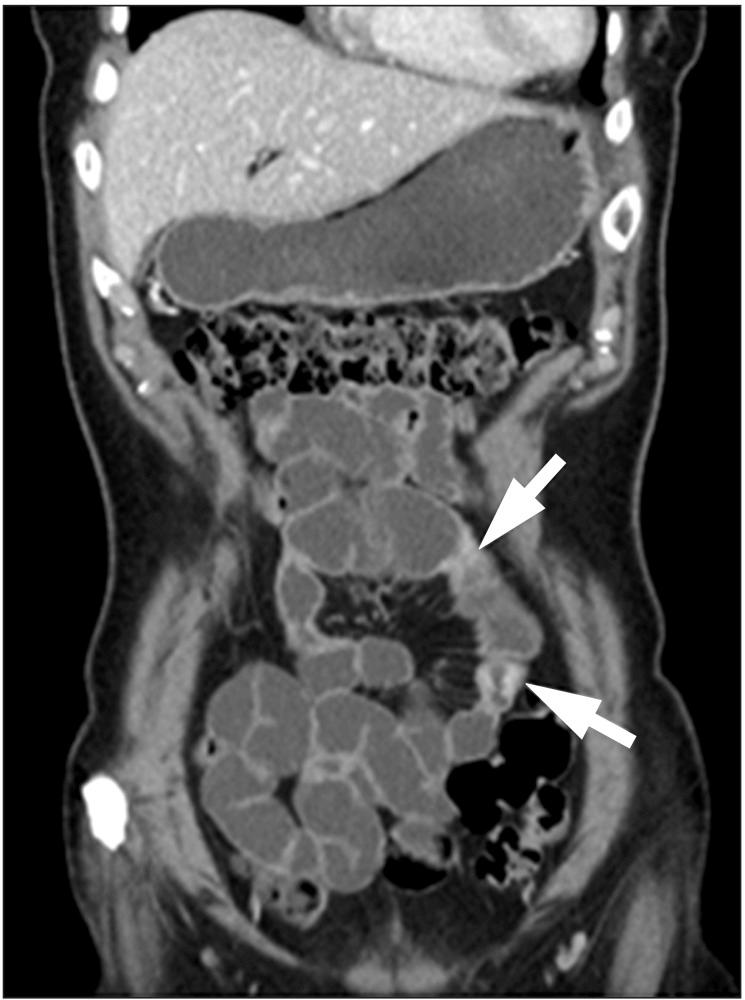

Since Taiwan is an endemic area for tuberculosis (TB), differential diagnosis between the intestinal TB and Crohn's disease is an important issue. The steering committee of Taiwan Society of Inflammatory Bowel Disease (TSIBD) has arranged a seminar accordingly on May 24th, 2014 and the different point of views by gastroenterologist, radiologist, pathologist and infectious disease specialist were suggested to help the proper diagnosis and management of these two diseases.

由于台湾是结核病的流行地区,肠结核与克罗恩病的鉴别诊断是一个重要问题。台湾炎症性肠病学会(TSIBD)指导委员会于2014年5月24日相应地安排了一次研讨会,并提出了胃肠病学家、放射科医生、病理学家和传染病专家的不同观点,以帮助对这两种疾病进行正确的诊断和管理。